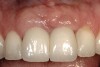

Figure 9  The final restorations exhibit a minimal 1-mm to 1.5-mm change in papilla height when compared with the pre-extraction height.

Figure 9